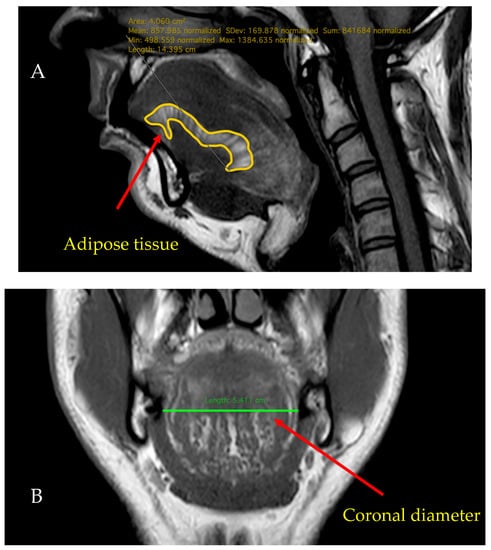

2.4. MRI

MRI measurements were carried out at the Medical Imaging Centre of Semmelweis University using a Philips Ingenia 1.5 T MRI device. MRI scans were conducted from the posterior nasal spine to the hyoid bone. As part of the neck MRI study, measurements of sagittal T2 TSE, STIR and T1 TSE, coronal T1 TSE (each with a slice thickness of 3.5 mm without gaps), and axial T2 SPIR, T1 TSE, and DWI (with a slice thickness of 3 mm with a gap of 1.5 mm) were performed. A Philips IntelliSpace Portal (Philips Healthcare, Best, The Netherlands) was used to analyse the scans and an experienced radiologist interpreted the results. The patients were examined in supine position and instructed to breathe normally through their noses.

The sagittal diameter of the tongue was measured in the anteroposterior directions, as the longest diameter between the apex and the base of the tongue. Tongue thicknesses were defined as the longest diameters between the origin of the genioglossus muscle and the surface of the tongue. Both calculations were based on T2 and T1 TSE weighted images.

The coronal and axial diameters were defined as the longest laterolateral diameters in the coronal or axial direction in coronal T1 TSE, axial T2 SPIR and T1 TSE scans. The midsagittal area (cm2) means the surface measured in the middle line of the sagittal axis, which was determined using the DICOM viewer software. The volume of the tongue was calculated using a semiautomatised analysis software (Philips IntelliSpace Portal Multi-Modality Viewer). The measurement was based on the calculation of the Region of Interest and volume rendering.

Tongue Fat% was defined as the ratio of the area on the midsagittal axis that shows the density of fat and the total surface of the tongue. In T1 weighted images, continuous adipose tissue in the tongue can be relatively well differentiated, and tongue Fat% was calculated using the fat area in the middle of the tongue using sagittal images and scaled to the midsagittal tongue area (Figure 2).

Figure 2.

(A,D) sagittal, (B) coronal, (C) axial T1 TSE MRI scans showing the anteroposterior, axial, coronal, sagittal, and midsagittal diameters, and also the calculation of Fat% (taken from our data).